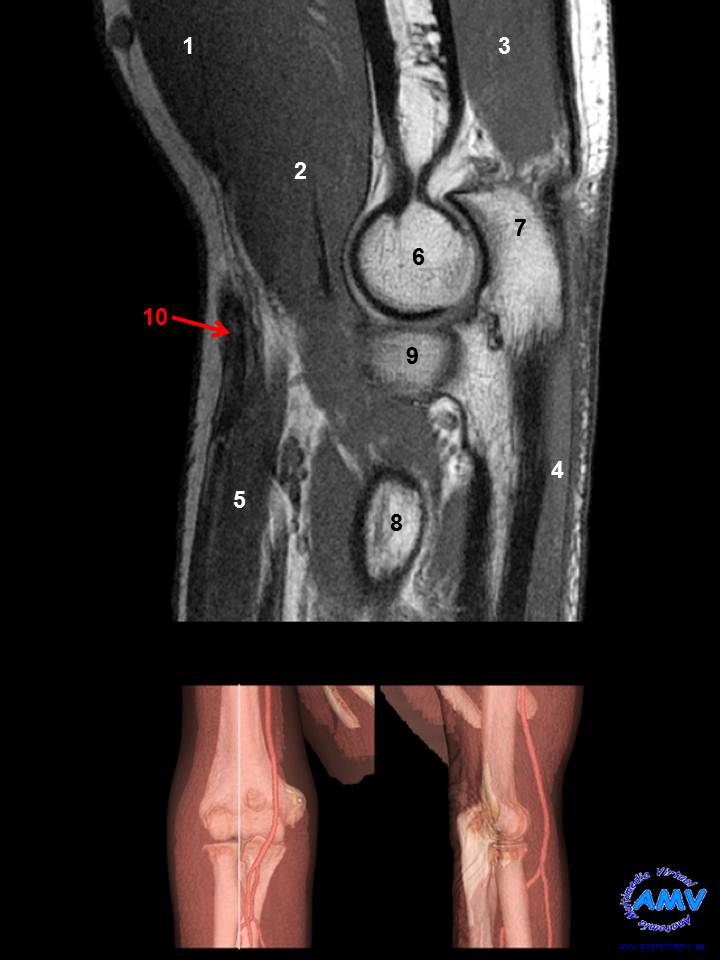

RMN Sagital de Codo

ms_rmn_07.jpgIndique que estructura se señala con el número correspondiente:

El nº 1 señala al músculo .

El nº 2 señala al músculo .

El nº 3 señala al músculo .

El nº 4 señala al músculo .

El nº 5 señala al músculo .

El nº 6 señala al hueso .

El nº 7 señala a la estructura ósea .

El nº 8 señala a la estructura ósea .

El nº 9 señala a la estructura ósea .

El nº 10 señala a la vena .